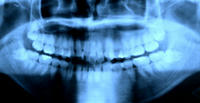

今行ってる臨床先でひょんな事から自分の口周りのレントゲン写真を撮って貰う事に。

今まで小さいの(通称デンタル)を撮った事はあっても、大きいの(通称パントモ)は撮った事がなかった。

↓フレアさんのお口周りのレントゲン~♪

まぁものの見事に親知らずがおりましたとさ。

下の歯がね。どー頑張っても正常に生えないって言う。。。